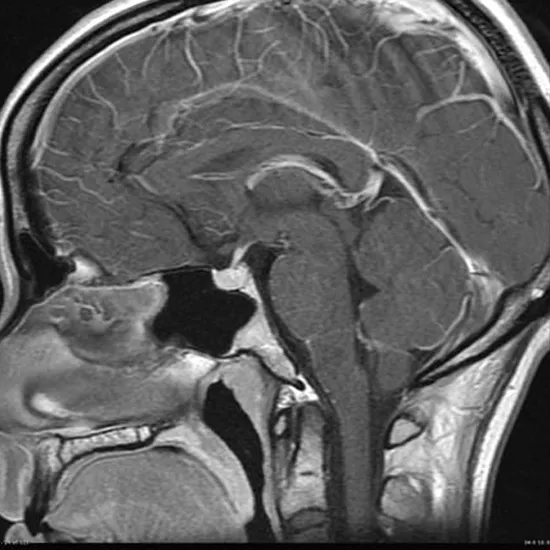

CECT Pituitary Gland is Contrast-Enhanced Computed Tomography of the Pituitary Gland. It is an imaging scan that uses X-ray beams and contrast media to obtain cross-sectional images of the pituitary gland. The pituitary gland is a small, bony nook gland located at the base of the skull.  This scan helps doctors to diagnose the abnormalities in the pituitary gland such as shrinkage of the pituitary gland, the existence of tumours, and other problems that are affecting the gland.

Doctors prescribe CECT Pituitary Gland To detect the problems in the pituitary gland such as shrinkage, flattening of the pituitary gland, the presence of tumours in the pituitary gland, and the root cause of hemianopia.